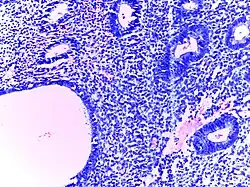

![]() |

Tuberculoid leprosy | Skin biopsy showing multiple peri-appendageal granulomas. | Category: Histopathology of leprosy | Leprosy |